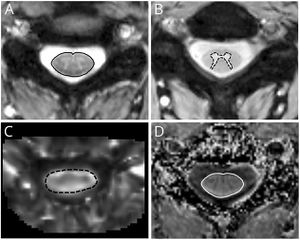

- 1.92 Quantitative Spinal Cord MRI in Radiologically Isolated Syndrome

Publication: Symmetry 2018 Nov 12; 10:627. | PDF Authors: Daniel Chalupa, Jan Mikulka. Institution: Department of Theoretical and Experimental Electrical Engineering, Brno University of Technology, Brno, Czech Republic. Abstract: The rather impressive extension library of medical image-processing platform 3D Slicer lacks a wide range of machine-learning toolboxes. The authors have developed such a toolbox that incorporates commonly used machine-learning libraries. The extension uses a simple graphical user interface that allows the user to preprocess data, train a classifier, and use that classifier in common medical image-classification tasks, such as tumor staging or various anatomical segmentations without a deeper knowledge of the inner workings of the classifiers. A series of experiments were carried out to showcase the capabilities of the extension and quantify the symmetry between the physical characteristics of pathological tissues and the parameters of a classifying model. These experiments also include an analysis of the impact of training vector size and feature selection on the sensitivity and specificity of all included classifiers. The results indicate that training vector size can be minimized for all classifiers. Using the data from the Brain Tumor Segmentation Challenge, Random Forest appears to have the widest range of parameters that produce sufficiently accurate segmentations, while optimal Support Vector Machines’ training parameters are concentrated in a narrow feature space.. Funding: